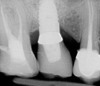

L’image radiologique post-opératoire montre les deux implants ancrés dans la poudre d’os qui a servi à combler le sinus maxillaire.